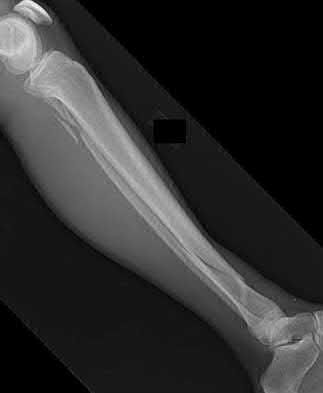

4. # After undergoing the treatment seen in Figure A, when should a patient be expected to safely operate the brakes of an automobile?

Corrent answer: 4

Figure A shows a patient after an open reduction and internal fixation of a bimalleolar ankle fracture.

Egol et al showed that by nine weeks, the total braking time of patients who had undergone fixation of a displaced right ankle fracture returns to the normal, baseline value.

Egol et al, also found that appropriate braking time returns at a point 6 weeks after initiation of weightbearing after treatment of lower extremity long bone and periarticular fractures, as examined with a driving simulator. No differences were seen in return of braking time between periarticular fractures and long bone injuries.